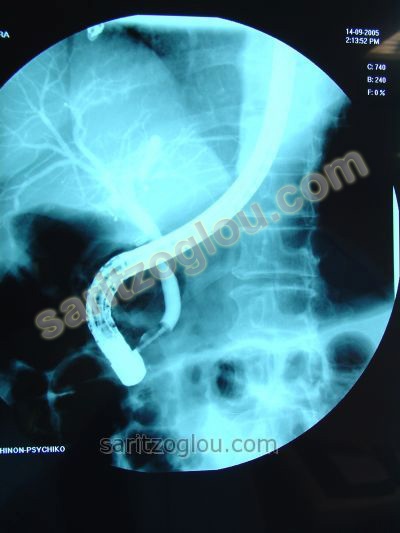

Στον προηγούμενο ασθενή, η πέτρα του χοληδόχου πόρου αφαιρείται με καθετήρα μπαλόνι. Ακτινοσκοπική εικόνα.

Στον ίδια ασθενή, η στιγμή της αφαίρεσης του λίθου από τον χοληδόχο πόρο. Ακτινοσκοπική εικόνα.